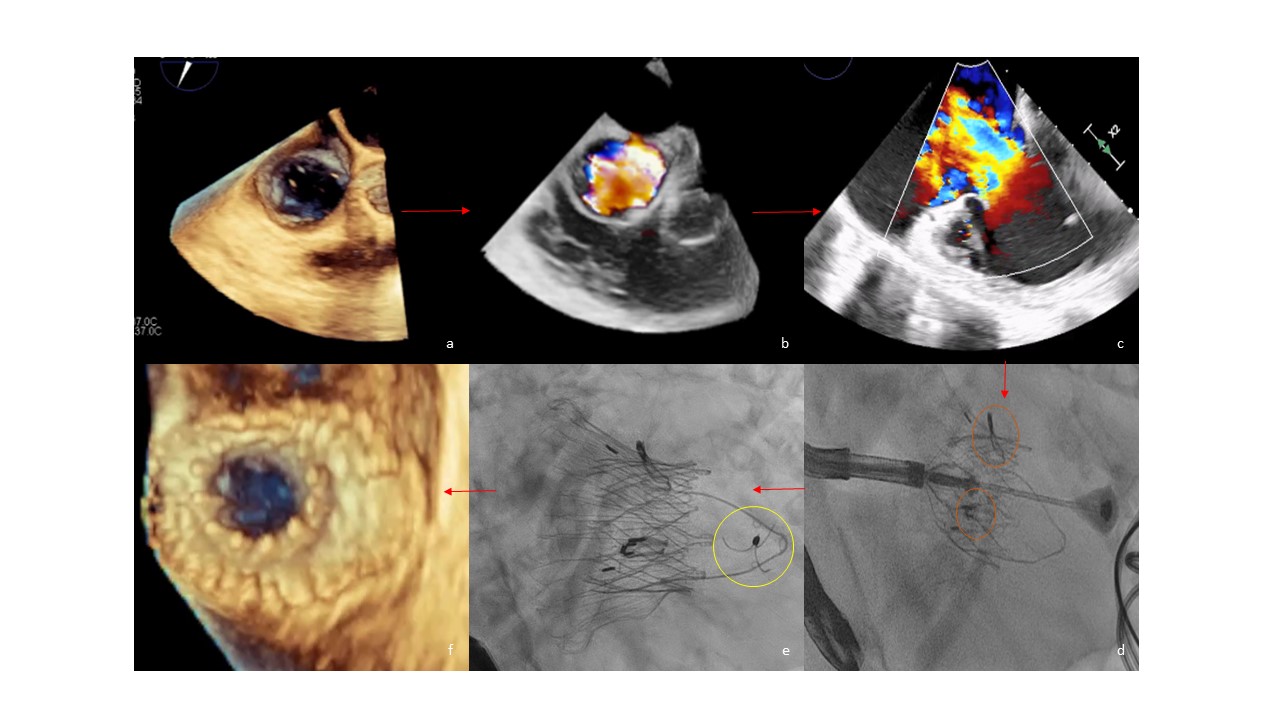

A 90-year-old woman with a history of metastatic small intestinal neuroendocrine tumor presented with worsening dyspnea, abdominal distention, and lower extremity edema, for which she was treated with somatostatin analogs and telotristat. Cardiac involvement was suspected after the development of progressive signs of right heart failure. An echocardiogram revealed massive TR (vena contracta: 30 x 34 mm; effective regurgitant orifice area: 2.7 cm2; regurgitant volume: 96 mL; and hepatic flow reversal), dilated right-sided chambers (right ventricular [RV] end-diastolic volume: 152 mL; RV end-systolic volume: 86 mL), and preserved right- and left-sided function (RV ejection fraction: 43.6%; fractional area change: 39%; left ventricular ejection fraction: 65%) (Figure A-C, Videos 1-4).

Figure. (A) Transesophageal echocardiogram (TEE) 3-dimensional (3D) image at 65o of the tricuspid valve annulus (area 15.2 cm2). (B) TEE image with 3D color Doppler showing the massive tricuspid regurgitation (TR). (C) TEE image at 0o depicting the massive TR. (D) The 2 ‘rabbit-ears’ graspers are seen clipping the leaflets (orange circles). (E) The LuX-Valve Plus (Jenscare Scientific Co. Ltd.) is released and the anchor has attached in the septum (yellow circle). (F) TEE 3D image at 70o showing the well-opposed prosthetic valve.